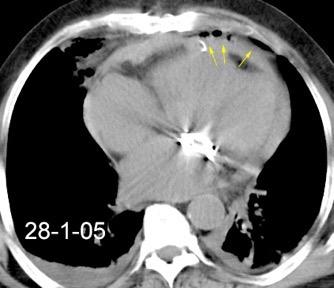

30 años

Borramiento de la banda PARA-aórtica por AdenoCa. de LII, no visible en 2005

Colapso de LII. TC: secreciones bronquiales.

Endoscopia tapón mucopurulento extraído